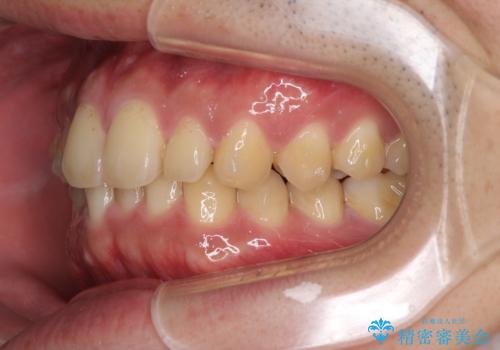

- 上下前歯のデコボコと下の前歯が隠れるほどの深い咬み合わせを気にして来院された患者様です。

インビザラインによる上下歯列の拡大と、IPR(歯と歯の間を削る)にるスペースの獲得により、口元のデコボコとディープバイトを改善することとしました。

デコボコがなくなったことで日頃の清掃が行いやすくなり、深い咬み合わせが改善したことで、食いしばりによる顎の負担も軽減されました。